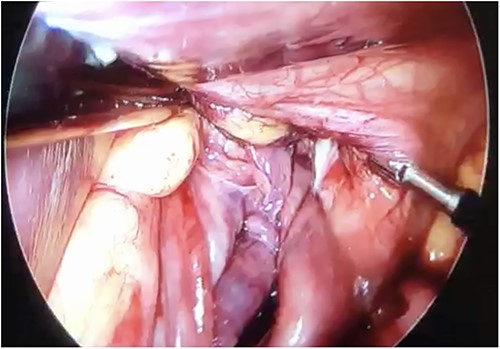

Initial treatment included intravenous crystalloid fluid repositioning, pain management, and antibiotic therapy. After diagnosing perforated gastric volvulus on a computed tomography (CT) scan, a diagnostic laparoscopy was performed. A hiatal hernia was identified with protrusion and twisting of the gastric body (Fig. 2). As the stomach body was reduced back to the abdominal cavity, a 1.5-cm perforation at the level of the greater curvature was detected. It was primarily sutured and covered with an omental patch (Fig. 3). The ischemic hernia sac containing the stomach was filled with food scraps and resected (Fig. 4). Laparotomy conversion was necessary due to hemodynamic instability attributable to the laparoscopic pneumoperitoneum. A 180° anterior fundoplication of the stomach (Dor’s Technic) associated with diaphragmatic raffia was performed. Gastric air leak testing was negative and intraoperative endoscopy showed no other defects on the gastric wall.

Twisted stomach body protruding through the diaphragmatic pillars, laparoscopic view.